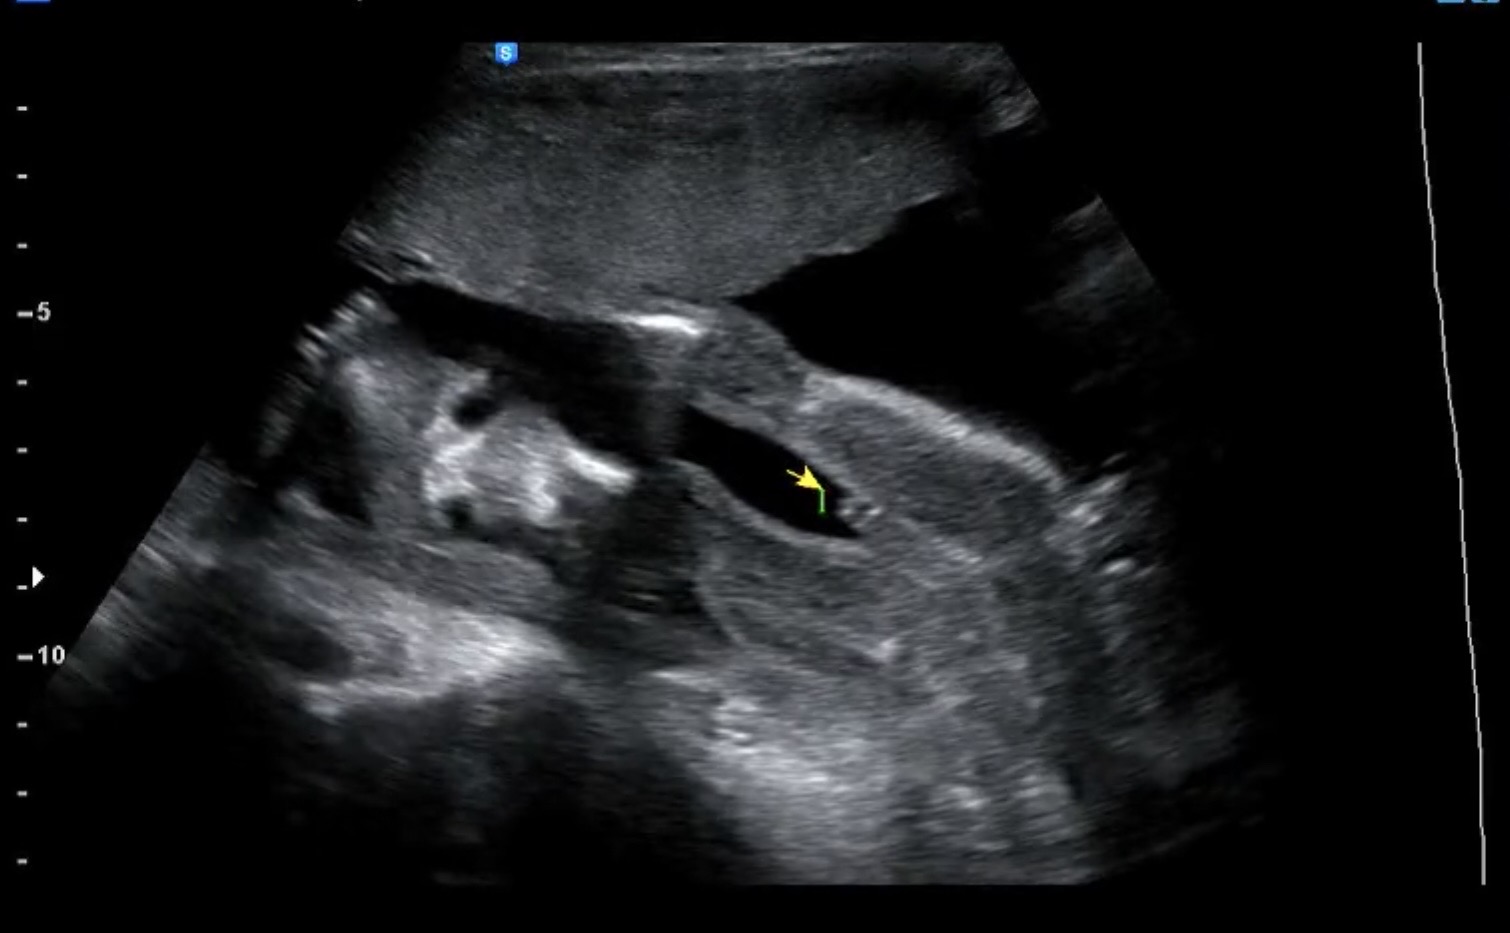

20주 초음파 성별 같이 봐주세요!

20주 5일차에요! 오늘 병원 갔는데, 아들인 것 같다고 하시는데~ 확실하게 말씀해주시진 않아서요! 이정도면 아들 맞겠죠? ㅎㅎ

완전 아들이용ㅋㅋㅋㅋ